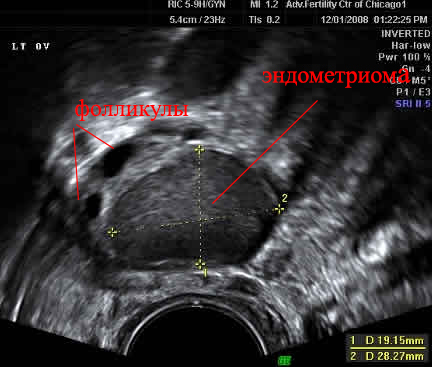

Эндометриоз может находится в любом месте в малом тазу: На брюшине, связках, кишечнике, мочевом пузыре. Он спаивает между собой органы и мешает им нормально функционировать. Он может находится внутри яичника (тогда он будет называться эндометриомой), своей плотной капсулой сдавливая сосуды и фолликулы, снижая качество яйцеклеток.

Эндометриома на УЗИ выглядит так: